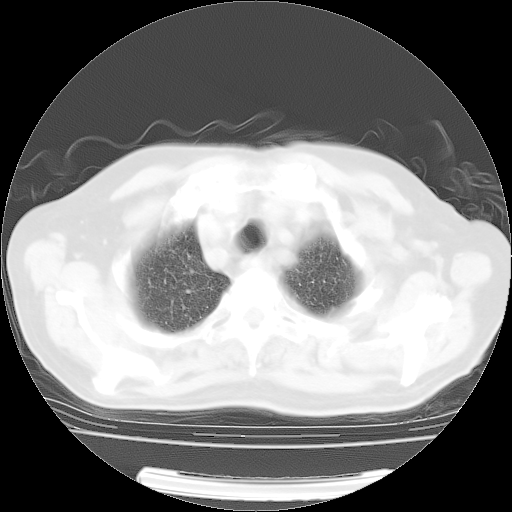

4月14日肺部CT

肺部CT平扫未见异常。